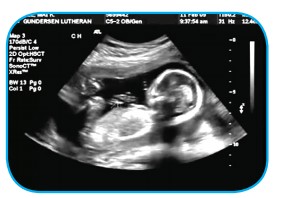

Ses yansımasının tıp alanında kullanımına ultrason cihazını örnek verebiliriz. Doktorlar hastalıkların teşhisinde, anne karnındaki bebeğin görüntülenmesinde ultrasonu kullanır. Bu aletle elde edilen görüntü ekrana aktarılır. Ultrason ses dalgalarından yararlanılarak geliştirilmiştir. Kulağımızla duyamadığımız sesi yayar, bu sesin iç organlarda yansıması ile ekranda oluşan görüntü ile iç organlarımız görüntülenmiş olur. Ultrason cihazı sayesinde iç organlarımızın görüntülenmesi sağlanır.